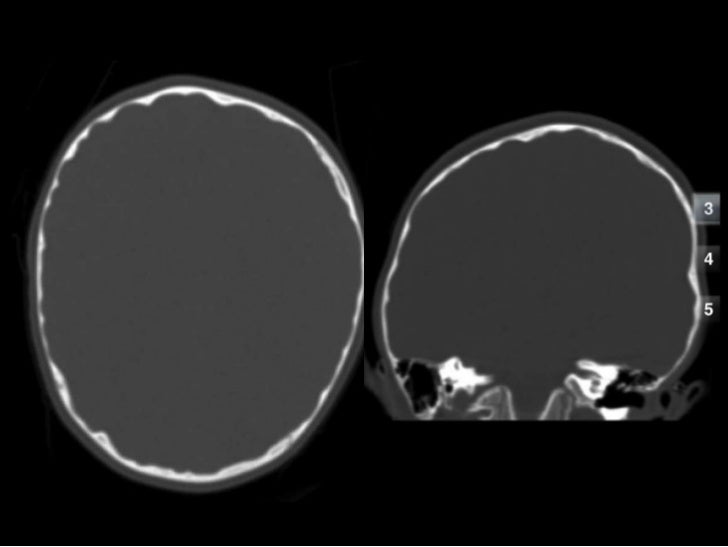

'copper beaten' skull refers to the prominent convolutional markings seen in multiple bones of the skull. Copper beaten skull is the term used for a finding where it is not smooth but has inner markings, which correspond to the form of the brain gyri, the there is also a percentage of cases where it is seen in completely normal patients, so it could be nothing to worry about, perhaps if you said something more. Skull radiograph demonstrates multiple small radiolucent areas with relatively round radiopaque markings around them, in a pattern similar to the at produced by beating on a sheet of metal with a small mallet. The ore is concentrated by froth flotation process. Even today, a lot of jewellery in india is.

As described above (and seen in the differential diagnosis case), convolutional changes may be normal if they are confined to the posterior calvaria and are subtle.

However, the copper beaten appearance of the skull has poor sensitivity in detecting increased intracranial pressure as such an appearance can also be seen in normal patients. Zurück zum zitat mahomed n, sewchuran t, mahomed z. A diffuse beaten copper pattern on skull radiographs, along with obliteration of anterior sulci or narrowing of basal cisterns in children under the age of 18 months, is predictive of increased intracranial pressure in over 95 percent of cases tuite and lindquist, 1996. Beaten copper appearance (hammered silver). Hoid appears as wit in the middle of the novel, discussing the nature of power with shallan. Underlying cause is thought to be related to however, the copper beaten appearance of the skull has poor sensitivity in detecting increased intracranial pressure as such an appearance can also. Copper beaten skull is a phenomenon wherein intense intracranial pressure disfigures the internal surface of the skull. Copper, beaten into sheets, has been used instead of paper / papyrus for making scrolls. Prior to that, while telling the story of mishim in alethkar, hoid sees something next to his pack, which startles him. Copper beaten skull is a phenomenon wherein intense intracranial pressure disfigures the internal surface of the skull. Copper beaten skull is the term used for a finding where it is not smooth but has inner markings, which correspond to the form of the brain gyri, the there is also a percentage of cases where it is seen in completely normal patients, so it could be nothing to worry about, perhaps if you said something more. Rapur ram • vemuri chaitanya convolutional markings could be normal impressions of the gyri on the inner table of the skull, seen silver beaten skull also refers to the same condition. Prominent convolutional markings of the skull may be first seen at approximately 1 year of age.

Hoid appears as wit in the middle of the novel, discussing the nature of power with shallan. A diffuse beaten copper pattern on skull radiographs, along with obliteration of anterior sulci or narrowing of basal cisterns in children under the age of 18 months, is predictive of increased intracranial pressure in over 95 percent of cases tuite and lindquist, 1996. Beaten copper appearance (hammered silver). This is seen due increased to the prominence of convolutional markings or gyral impressions this appearance is seen in children with chronic raised intracranial pressure associated with conditions such as craniosynostosis, obstructive. The cbk appearance is typically associated.

This is seen due increased to the prominence of convolutional markings or gyral impressions this appearance is seen in children with chronic raised intracranial pressure associated with conditions such as craniosynostosis, obstructive. The molten copper is poured out and allowed to cool. If you continue browsing the site, you agree to the use of cookies on this website. 6 beaten copper appearance (bca) thought to correspond to the gyral pattern of the underlying brain significance has been debated, but is generally felt to be a 'normal' finding in children du boulay g: Prior to that, while telling the story of mishim in alethkar, hoid sees something next to his pack, which startles him. Zurück zum zitat mahomed n, sewchuran t, mahomed z. The appearance is called copper beaten skull or brass beaten skull. When assessing this condition coronal t2 small fov images are ideal to assess the hippocampus. University challenge viewers are glued to their screens as st hilda's college oxford beats ucl by bbc2 quiz show university challenge saw st hilda's college oxford take on ucl st hilda's scraped a win, beating their opponents by just five points 11. Even today, a lot of jewellery in india is. Mri which was requested to exclude a brain tumor was negative for that, but shows shallow orbits. Slideshare uses cookies to improve functionality and performance, and to provide you with relevant advertising. The significance of digital impressions in children's skulls.